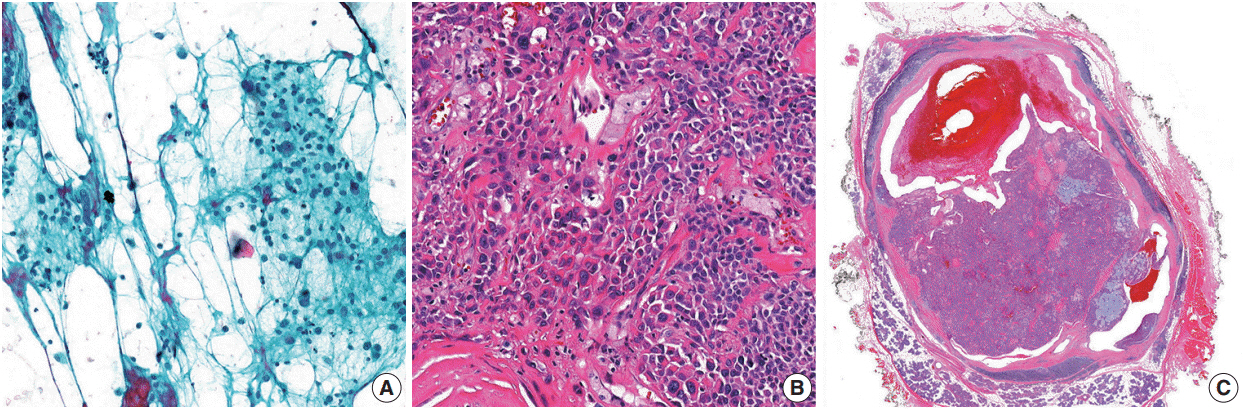

Figure